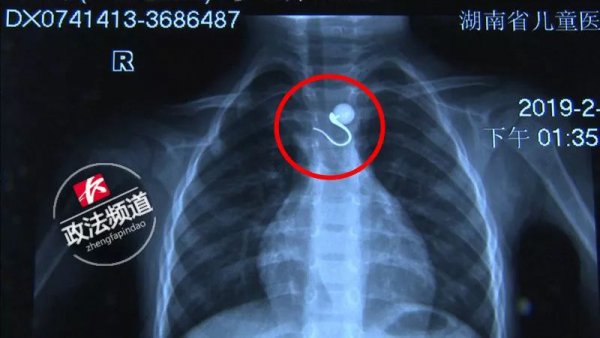

近日,涟源的杨女士给1岁10个月的儿子龙龙(化名)换尿布时,孩子拿起放在一旁的珍珠耳环就往嘴里放,而杨女士低头忙着换尿布,并没有注意到龙龙的危险行为,等到换完尿布这才发现,龙龙捂住喉咙已经发不出声来。

杨女士意识到龙龙是误吞了珍珠耳环,赶紧把他送往医院。

经过医生紧急处置,被卡在孩子喉咙里珍珠耳环被成功取出。